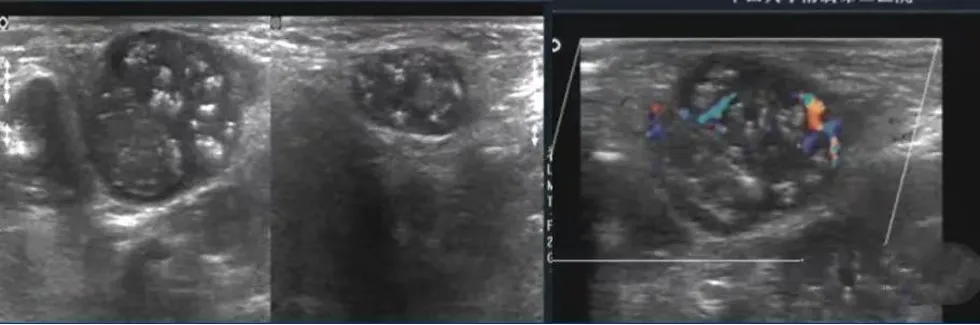

左腋下淋巴结结核样肉芽肿性炎并坏死及钙化。

病例:1岁男孩,发现腋窝包块2个月,质地较硬,患儿无明显发热。

超声描述:左侧腋窝可见两个混合回声团,边界清楚,内部回声不均匀,可见多个强回声点,未见明显淋巴结结构。内部见杂乱血流信号。